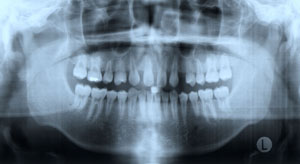

15세 7개월 된 남학생이 상악전치부 spacing을 주소로 내원하였다. 방사선사진을 촬영하고 상·하악 인상을 채득한 후 통상적인 방법으로 교정진단을 한 결과 다음과 같은 problem을 갖는 것으로 진단되었다 (그림 1,2).

그림 1. 15세 7개월 된 남학생의 내원시 구강내 모습으로 상악 좌우 측절치 결손으로 전치부 spacing을 나타내고 있다.

측모두부방사선규격사진에서는 상악골이 다소 돌출되어 있는 양상을 보이고 있는 것 외에는 두드러진 문제가 보이지 않았다. 파노라마 사진에서 상악중철치의 치근이 짧은 것이 눈에 띄었으며 좌우 견치가, 특히 좌측 견치가 견치위치라기보다는 측절치 위치에 자리잡은 것으로 나타났다. 석고모형 분석 결과 상악의 공간 양은 약 16mm로 측정되었으며 개개 치아크기를 평균치와 비교시 상악 양 중철치가 두드러지게 작은 것을 알 수 있었다. 반면 하악은 정상적인 배열을 보였다. 상·하악 교합 분석시 좌측은 정상적인 Cl I을 보였으나 하악 치열 정중선의 우측 편위와 함께 우측교합은 Cl II를 나타내었다. OB과 OJ은 3.0과 3.5mm로 정상보다 1.0 또는 1.5mm 큰 양상을 보였다 (그림 2,3).